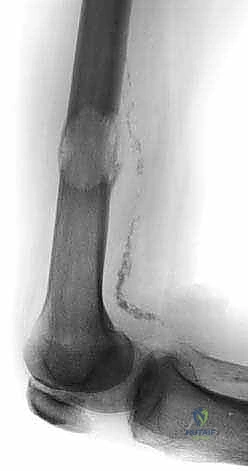

- الأشعة السينية العادية (X-rays): هي الخطوة الأولى دائماً. تظهر النقائل الحالة للعظم كبقع داكنة (ثقوب) في العظم، بينما تظهر النقائل البانية كبقع بيضاء كثيفة. الأشعة السينية ضرورية لتقييم خطر الكسر.

- التصوير المقطعي المحوسب (CT Scan): يقدم تفاصيل ثلاثية الأبعاد لا مثيل لها لجودة القشرة العظمية المتبقية. يساعد الجراح في التخطيط لحجم المسامير أو الصفائح المطلوبة، وتقييم مدى تدمير العظم.

* النقائل الحالة للعظم (Osteolytic): (مثل سرطان الثدي والرئة والكلى) تؤدي إلى تدمير مفرط للعظم، مما يتركه مليئاً بالفجوات وهشاً للغاية وقابلاً للكسر بسهولة.